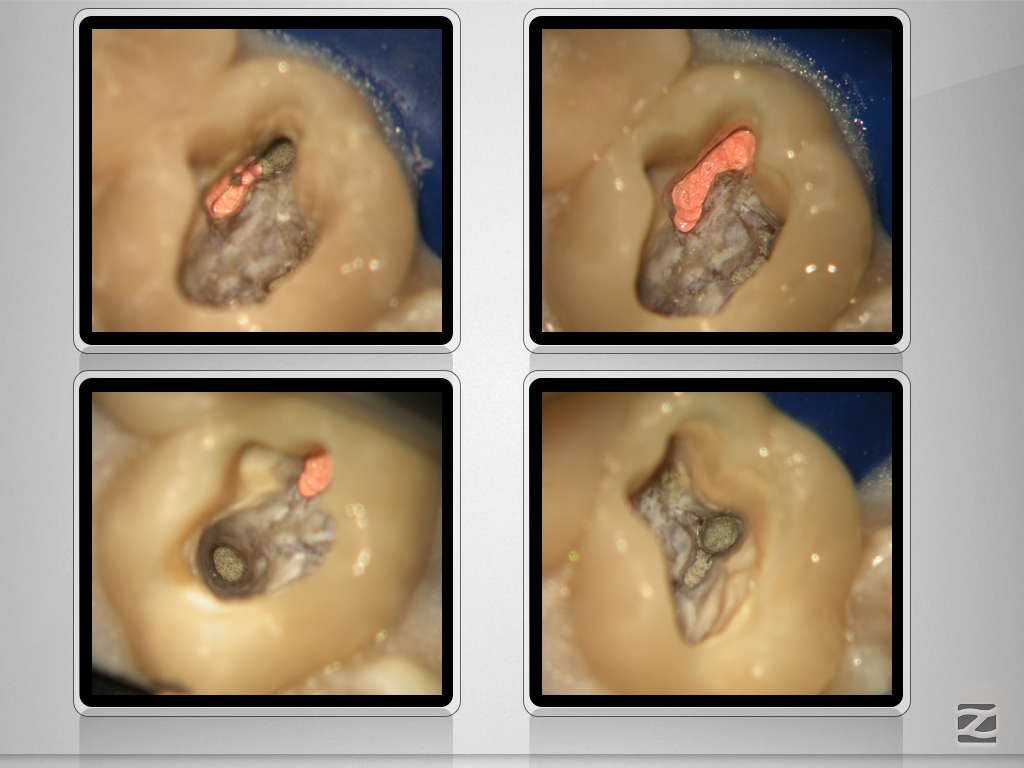

16d-012

Revision nach Resektion